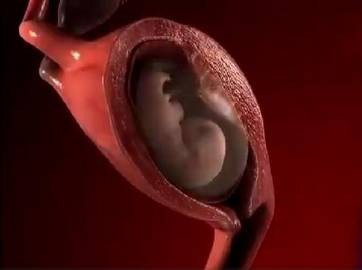

妈妈从孕育到孩子的出生,中间要经历10个月。网上有一组生动形象的动图,可以看出这十个月妈妈究竟经历了什么,这个期间,宝宝每个月在妈妈的肚子里的状态都是不一样的。如果有看过一个胎儿从开始孕育到出生10个月的不同形态,你就会感受到生命的神奇,宝宝在妈妈肚子里每个月不同的形态。

孕妈在刚刚怀孕的时候,宝宝那会儿还只是一个胚胎,被子宫包裹住也就只有鸡蛋那么大。如果孕妈反应激烈,呕吐恶心,这个时期的孕妈是非常难受的。

当宝宝在妈妈肚子里呆到第二个月的时候,胎儿从一个胚胎变成了雏形,而且孕妈的子宫壁也会越来越薄。

这个时候,其实是胎儿发育最快的时期,基本上已经占满了妈妈的整个子宫。孕妈的子宫就会变得很大,还会压迫到膀胱,从这个时候开始就会有尿频的感觉,去厕所次数越来越多,而且肚子也会明显的凸出来。